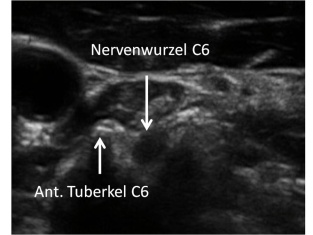

Ultraschall-gesteuerte foraminale Infiltration einer cervikalen Nervenwurzel

Bei radikulären Schmerzen bei cervikaler Diskushernie können die Nervenwurzeln auch Ultraschall-gesteuert und damit ohne jegliche Strahlenbelastung extraforaminal infiltriert werden. Mit entsprechender Übung gelingt dabei trotz extraforaminaler Punktion eine transforaminale epidurale Medikamentenausbreitung, wodurch das Risiko der zwar seltenen, aber schwerwiegenden Komplikationen dieser Intervention gesenkt werden kann.